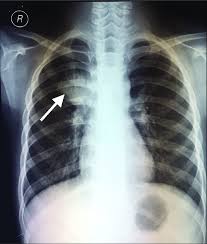

Case contributed by dr brenda lee solorzano frontal chest x ray shows bilateral micronodular insterstitial effusion. At the description of these shadows it is. Tb is an airborne disease caused by the bacteria mycobacterium tuberculosis and mycobacterium bovis. Thus chest x rays are neither specific nor sensitive and so remain a supplement to microbiological tests such as microscopy pcr and culture. A practical manual for preventing tb, 2011. Tuberculosis of intrathoracic lymphatic nodes 3.2.3. Culture was used as gold standard. Left apical bronchiectasis at the level of.

Tuberculosis without established localization the greatest difficulties arise at diagnosing tubercular intoxication and small formsof lymphatic nodes. From point ai to point tb: The samples are tested for tb bacteria. Abnormalities on chest radiographs may be suggestive of, but are never diagnostic of tb, but can be used to rule out pulmonary tb. Case contributed by dr brenda lee solorzano frontal chest x ray shows bilateral micronodular insterstitial effusion. For decades, tuberculosis (tb), a potentially serious infectious lung disease, continues to be a leading cause of worldwide death. From tb suspects attending a chest clinic in nairobi, kenya, three sputum specimens were examined for zn and culture (lowenstein jensen). On radiograph tubercular lesions of lung parenxyma, stroma comes to light as shadows (densities, consolidations).

A practical manual for preventing tb, 2011. Tuberculosis without established localization the greatest difficulties arise at diagnosing tubercular intoxication and small formsof lymphatic nodes. The samples are tested for tb bacteria. Tuberculosis of intrathoracic lymphatic nodes 3.2.3. Tb is an airborne disease caused by the bacteria mycobacterium tuberculosis and mycobacterium bovis. Case contributed by dr brenda lee solorzano frontal chest x ray shows bilateral micronodular insterstitial effusion. On radiograph tubercular lesions of lung parenxyma, stroma comes to light as shadows (densities, consolidations). From tb suspects attending a chest clinic in nairobi, kenya, three sputum specimens were examined for zn and culture (lowenstein jensen). Thus chest x rays are neither specific nor sensitive and so remain a supplement to microbiological tests such as microscopy pcr and culture. Culture was used as gold standard. Tuberculosis a manual for medical students. Left apical bronchiectasis at the level of. At the description of these shadows it is.